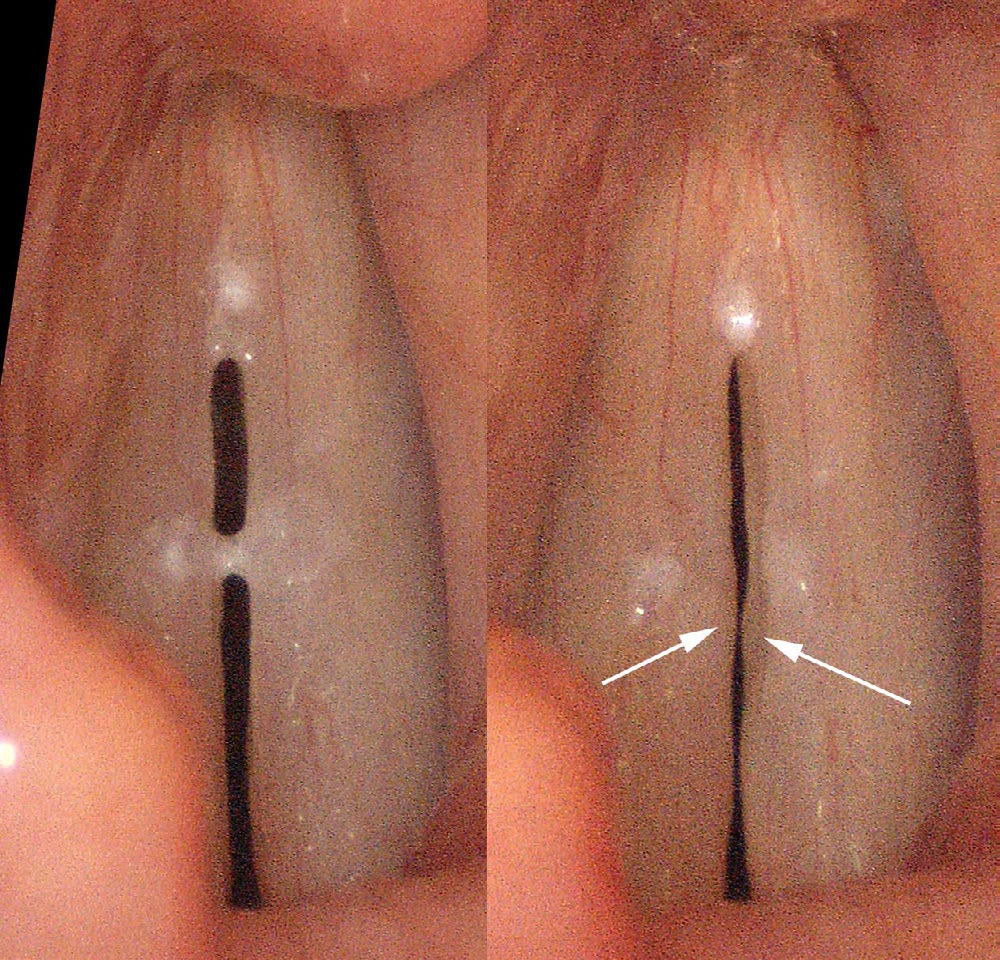

For the dedicated examiner, secretions quite often act as a divining rod, pointing to where a lesion will be found, rather than hiding it.

More commonly than actual thick mucus, I find that secretions tend to accumulate anywhere on the vocal cords where vibrations are impaired. For example, a person with a polyp, nodule or other swelling will tend to accumulate mucus on the polyp while they are making sound and have to constantly clear it off the vocal cords. People with weak, thin or bowed vocal cords will tend to have secretion accumulation at the ends of the vocal cords where they come together. If the impairment of vibration is corrected, fewer secretions will accumulate.